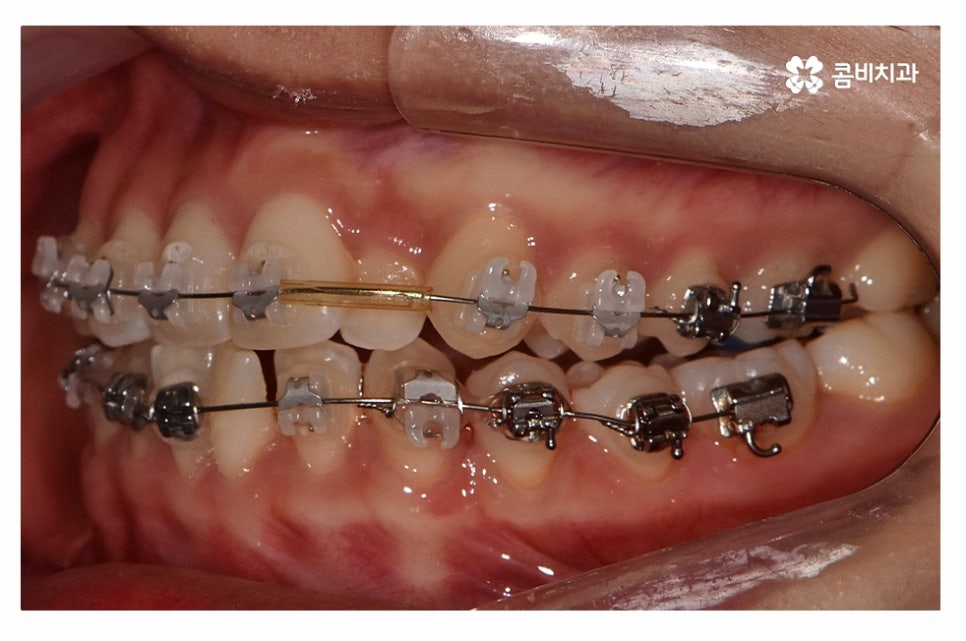

오늘 보여드릴 사례도 덧니교정이 비발치로 진행이 된 사례이며

치아의 이동 공간과 치아 상태, 골격, 얼굴형 등을

종합적으로 판단할 때 비발치로도 진행이 가능했던 사례라고 할 수 있어요.

위 환자분의 사례처럼 클리피씨교정이 보편적으로 많이 활용되고 있는데요.

클리피씨교정은 치아의 이동이 일반 장치에 비해 상대적으로

빠르기 때문에 치료 기간이 단축될 수 있으며

통증의 감소, 내원 횟수를 줄일 수 있다는 장점 등이 있어요.